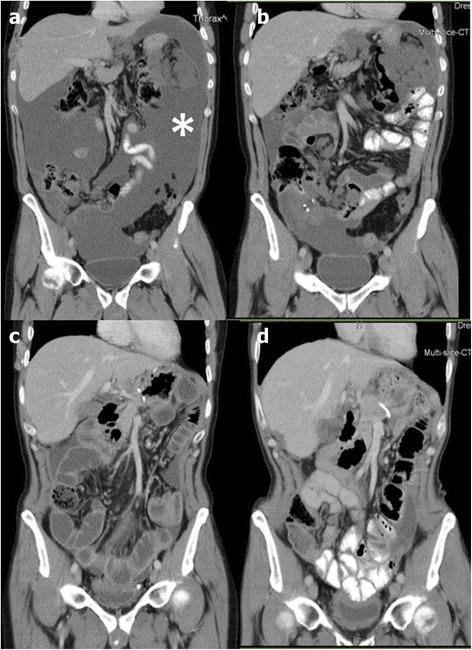

Nine-hundred sixty-one PIPAC sessions were successfully performed in 406 patients: 21 patients (5.2 %) were scheduled for CRS and HIPEC. Twelve of these patients had a low PCI (mean 5.8 ± 5.6). The remaining nine patients showed an advanced peritoneal disease (mean PCI 14.3 ± 5.3) at initial laparoscopy. After repeated PIPAC (mean number of cycles 3.5 ± 0.9), radiological tumor regression was observed in 7/9 patients and major histological regression was observed in 8/9 patients, so that secondary CRS and HIPEC became possible.

406例患者成功进行了961次PIPAC治疗:21例患者(5.2%)计划接受CRS和HIPEC。其中12例患者的腹膜癌指数(PCI)较低(平均5.8±5.6)。其余9例患者在初次腹腔镜检查时显示为晚期腹膜疾病(平均PCI 14.3±5.3)。经过反复PIPAC(平均周期数3.5±0.9)后,7/9的患者出现影像学肿瘤消退,8/9的患者出现主要组织学消退,从而使二次CRS和HIPEC成为可能。